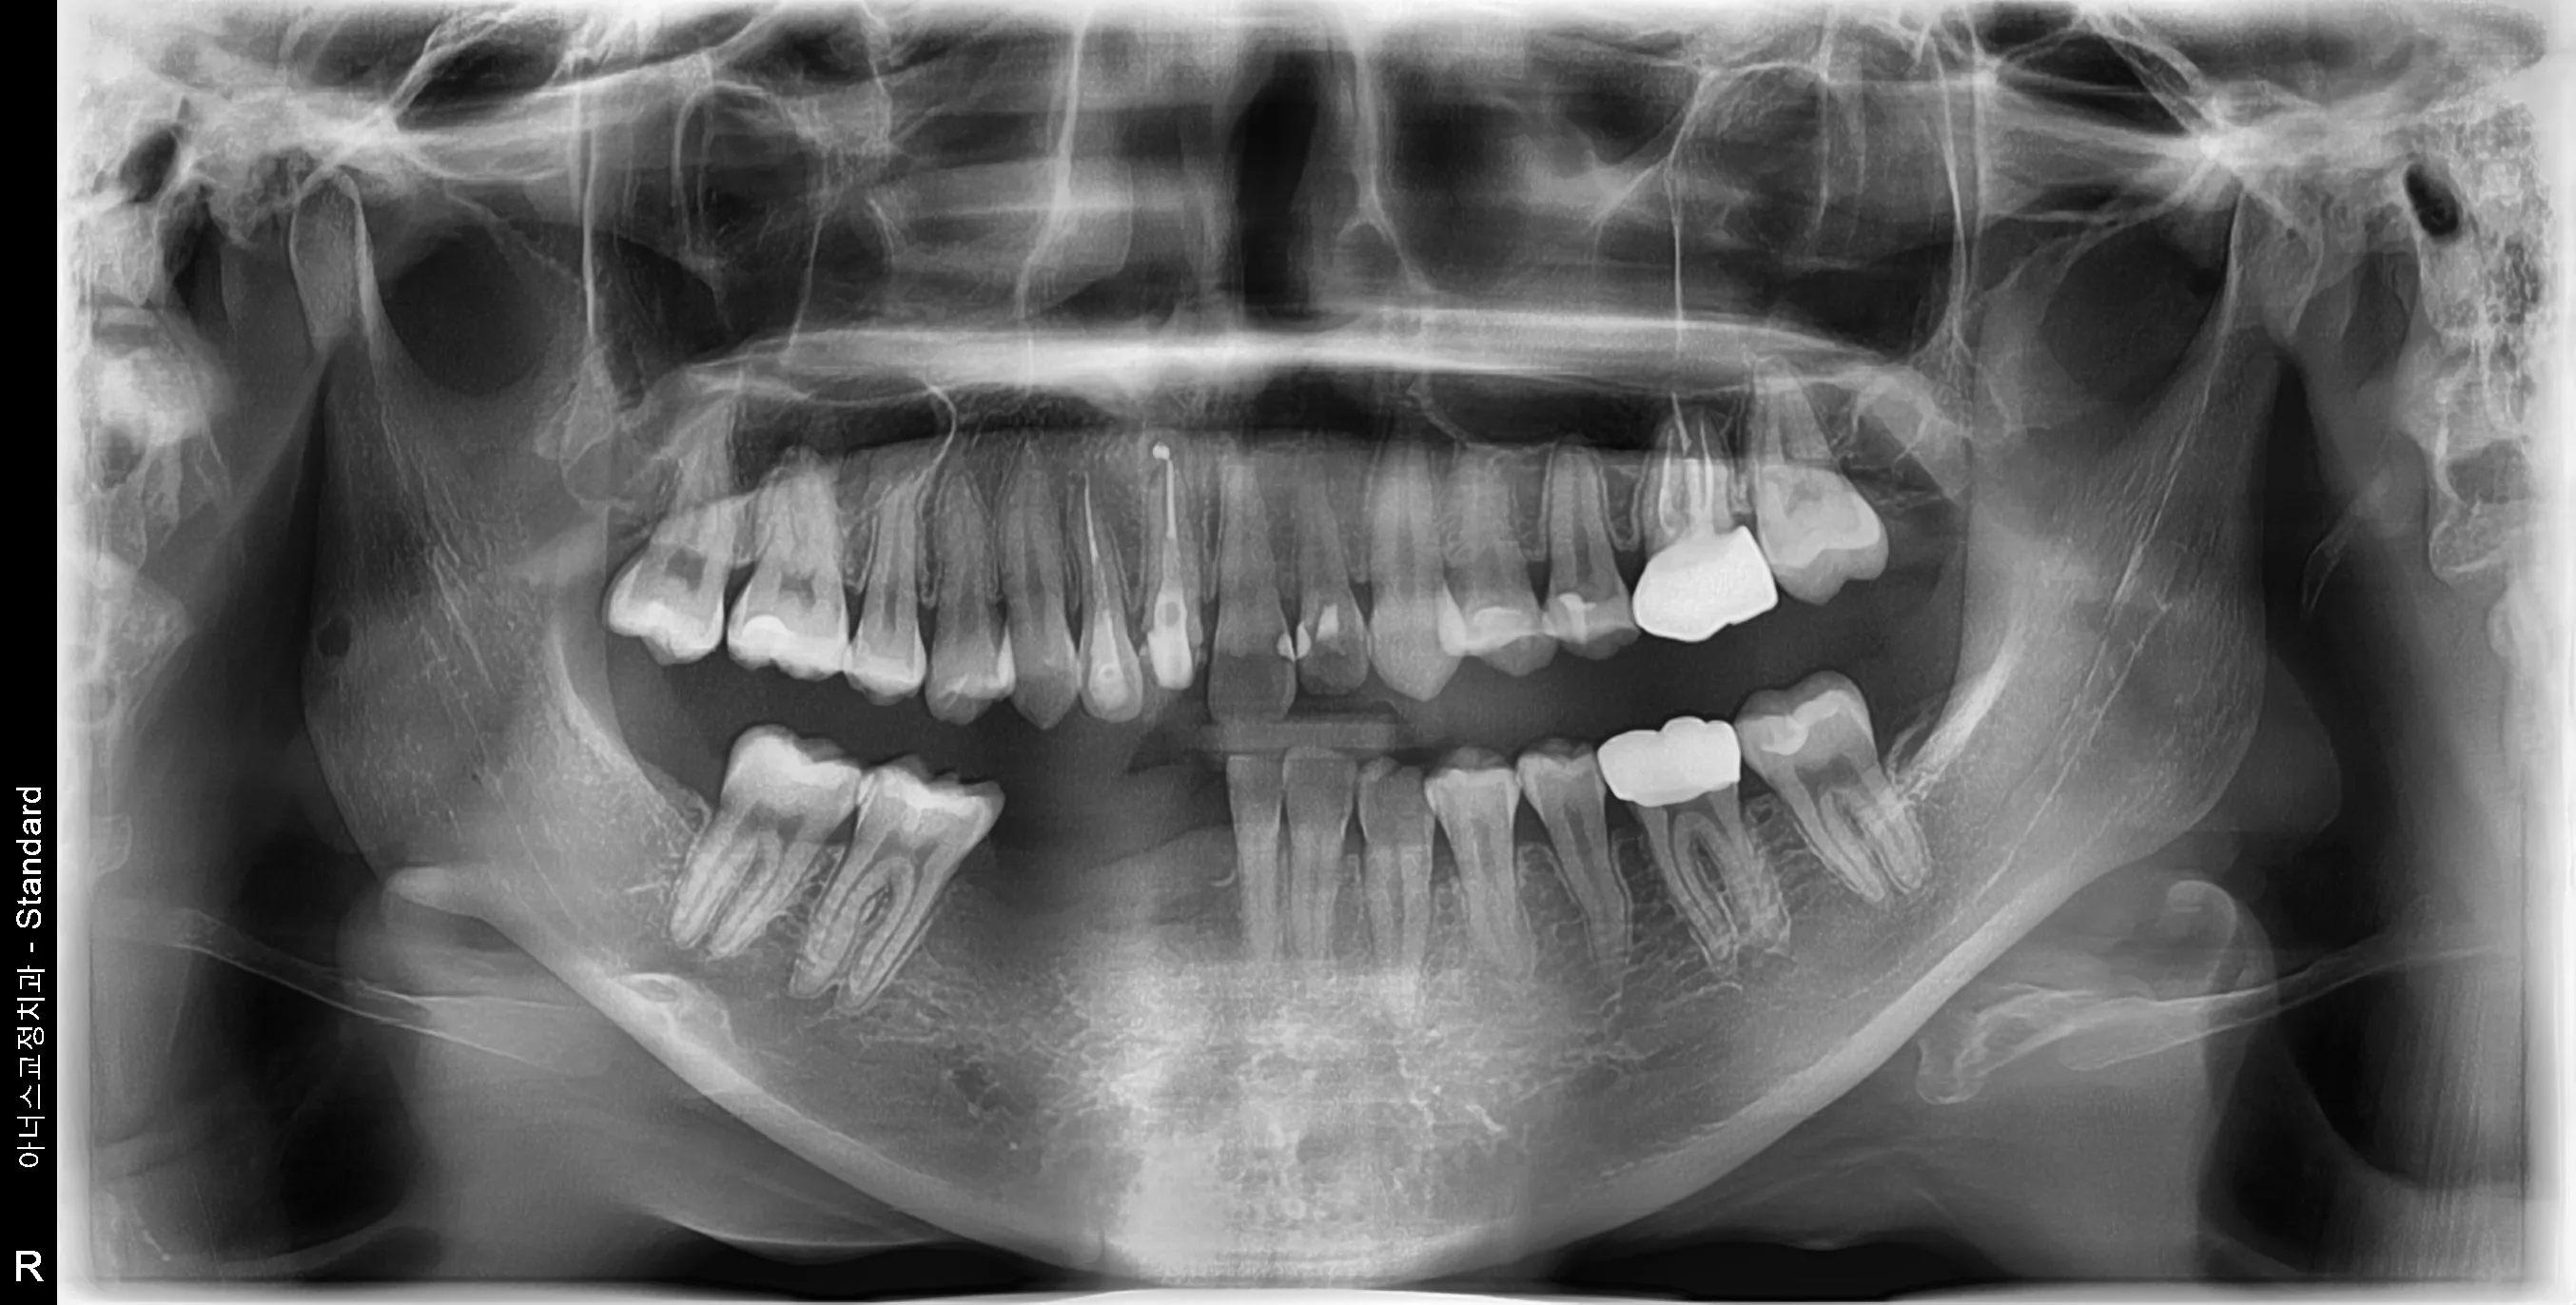

만 21세 환자로, 기존에 사고로 여러 치아를 다치고 상실한 상태로 매우 심한 교합무너짐이 있었습니다.

엑스레이

치료전 (Before)